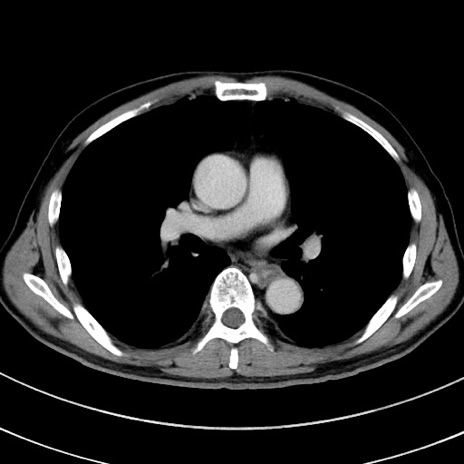

症例8(横断像)

【症例】 60歳代男性

【主訴】 黒色吐物

【現病歴】 4日前から嘔気自覚、2日前の朝食後にも嘔気あり、自分で手で嘔吐反射起こし嘔吐したところ血が混ざっていたため受診。

【既往歴】 5年前汎発性腹膜炎を伴う急性虫垂炎で手術、高血圧、前立腺肥大症、高脂血症

【身体所見】 腹部正中に手術癩痕あり 腹部平坦・軟圧痛なし膨満感あり

【データ】WBC 8400、CRP 4.54